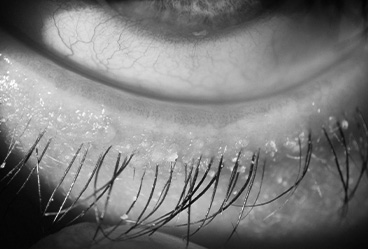

• Imaging the lid margins - Detects Demodex, Blepharitis and Ocular Rosacea.

Zest is a gentle, deep-cleaning treatment for your eyelids and lashes that removes oils, debris, and bacterial biofilm—like a “deep shampoo” for your eyelids. It helps reduce inflammation from dry eye and blepharitis while soothing discomfort.

Performed by our ocular hygienists, the treatment begins with a warm eye mask and relaxing music, followed by an okra-infused gel applied to gently exfoliate the eyelid margins and clear debris, bacteria, and Demodex. The procedure is painless, similar to a dental cleaning for your eyes.

Demodex

Demodex are tiny mites that commonly reside in our hair follicles and sebaceous glands.

The cause of chronic blepharitis can sometimes be secondary to a Demodex infestation of the eyelid follicles. Your optometrist will be able tell by examining your eyelashes if there is an overpopulation of the demodex mites.